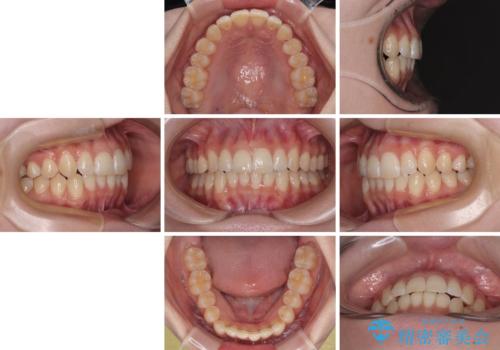

気になる前歯と咬み合わせを改善 インビザライン・モデレート

- 上下前歯の重なりを気にして来院された患者様です。

安価なインビザラインパッケージを用いての治療を希望されており、デコボコの程度が中等度であったため、インビザライン・モデレートを用いて矯正治療を行うこととしました。